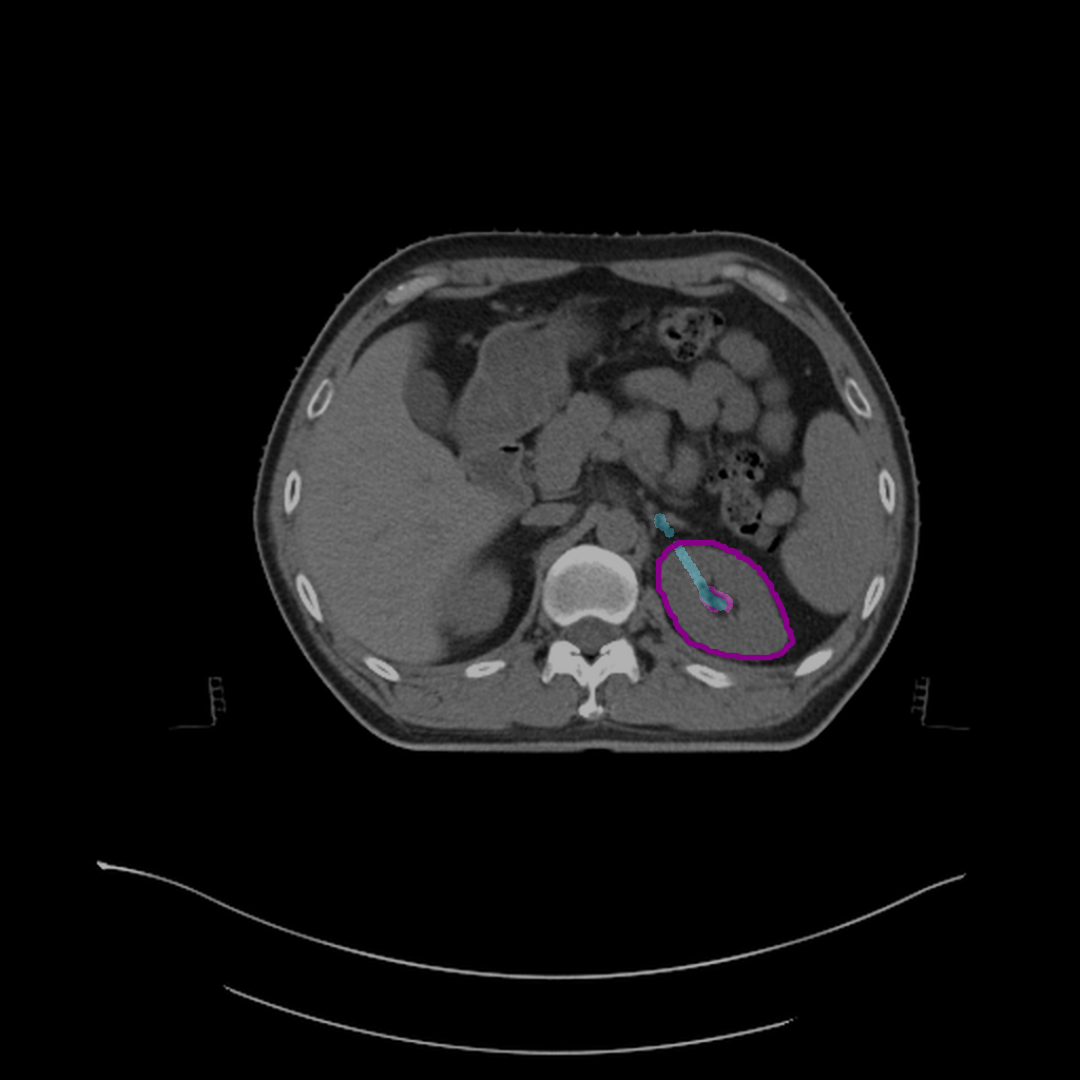

Refer to caption

(d) Initial predicted mask.

(e) Mask after half correction.

Figure 4: Steps to correct segmentation masks for various abdominal organs, such as the spleen, left kidney, and liver, on different CT slices. Each subfigure shows the outline of reference segmentation contours, the predicted segmentation mask, and gaze points (blue) used for predictions based on gaze.